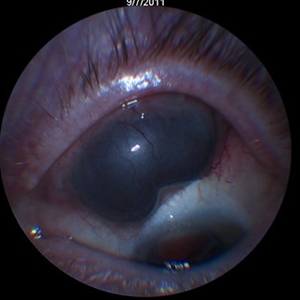

Ciliary mass

Patient presented with mass hidden by upper lid, 20/30 vision

Condition/keywords: ciliary body mass